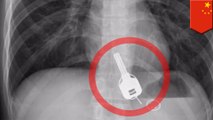

Chinese guy swallows keys during bender, has them taken out